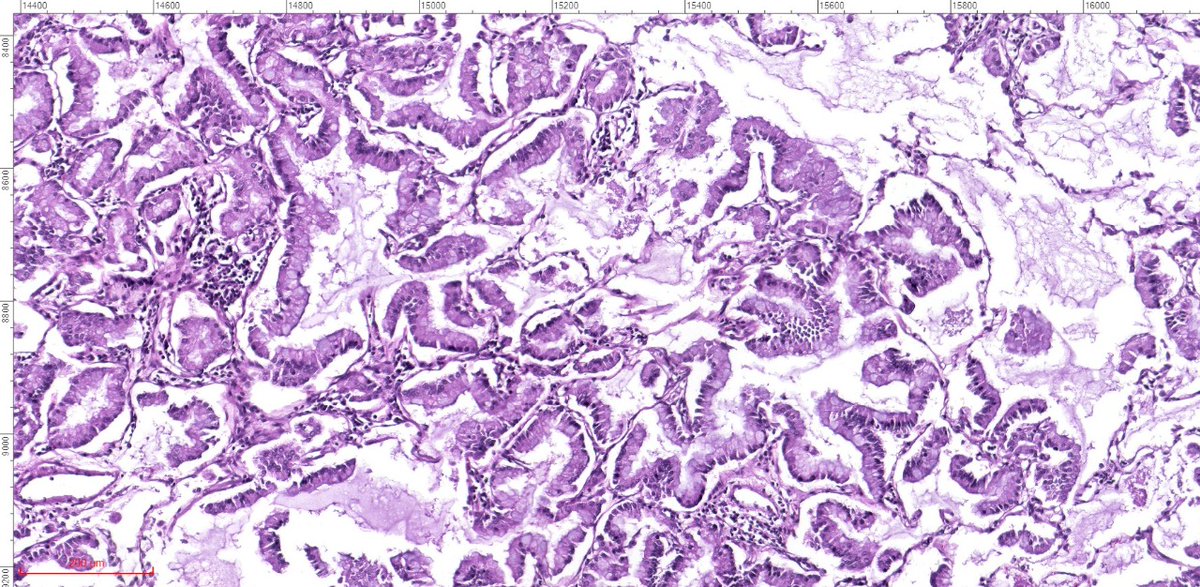

🔬#PulmonaryPath: What's Your #DailyDX? ➡️ The most frequent type of lung cancer, about 50%. ➡️ Also most prevalent in cancer types: prostate, pancreatic, esophageal, and colorectal. ➡️We’ll tweet the answers, some quick facts, and the next case tomorrow! #UMichPath

➡️ The most frequent type of lung cancer, about 50%.

➡️ Also most prevalent in cancer types: prostate, pancreatic, esophageal, and colorectal.

➡️We’ll tweet the answers, some quick facts, and the next case tomorrow! #UMichPath